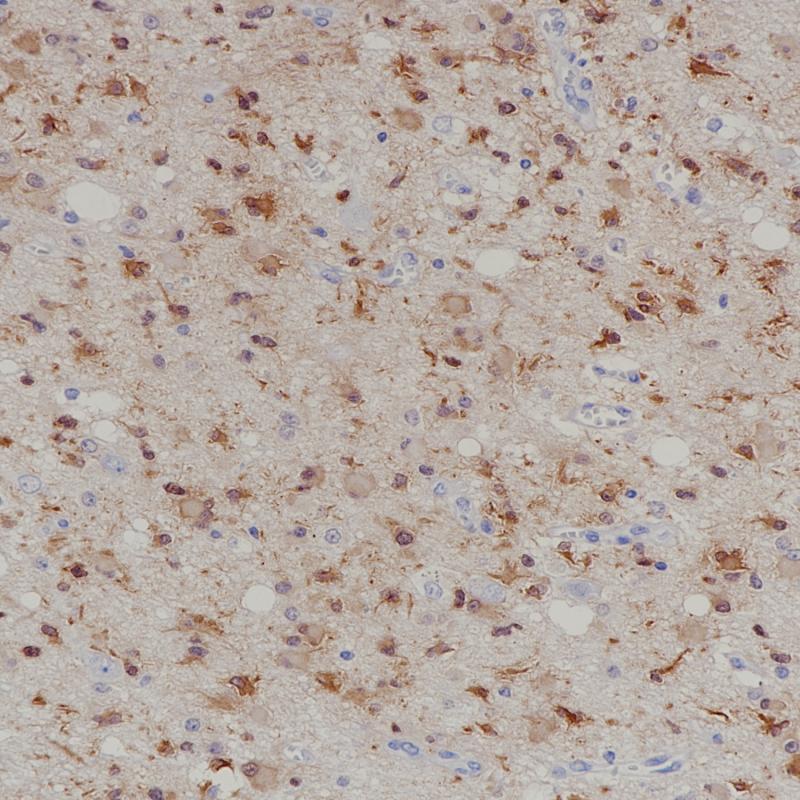

Myelin Basic Protein

BP6087